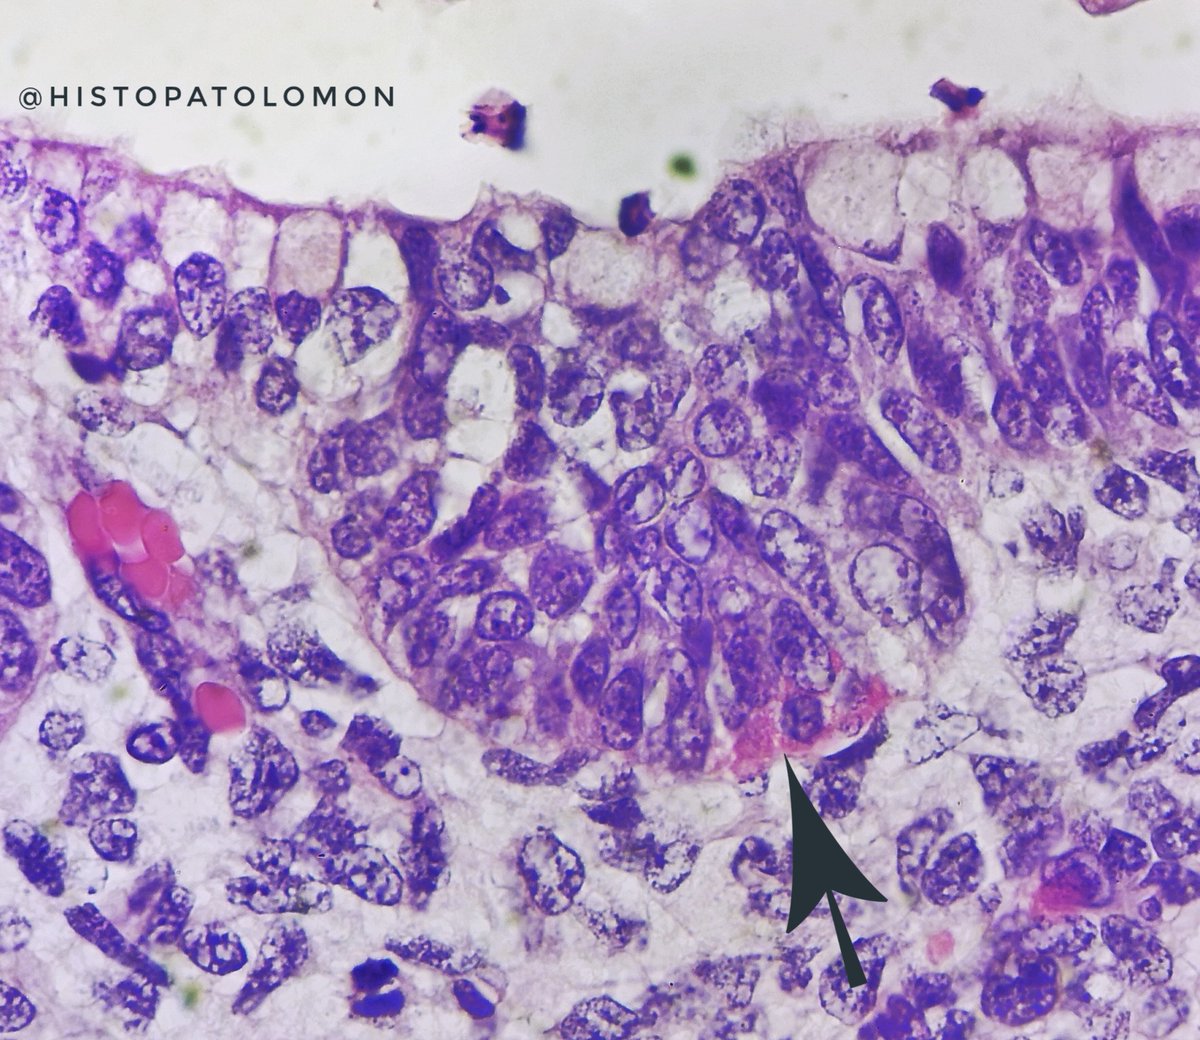

Neuroendocrine cells also appear at 7 weeks. Here we see them with their granules, next to the basement membrane.